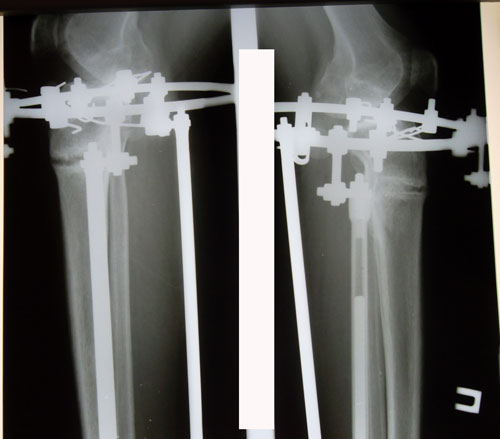

Рентген в 121 день. Снимать аппараты рановато, ждём ещё месяц. Делаем повторный рентген и смотрим. Можно снимать не 10 апреля, а на несколько дней раньше. кушайте творог, мясо, кальций, холодец, мумиё (как учили в клинике) и позитивное настроение! 04000000.